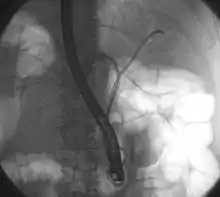

![]() Tumor de Klatskin durante ERCP. El paciente yace sobre su estómago de manera oblicua, por tanto el lado izquierdo de la imagen corresponde al lado izquierdo del paciente. A la izquierda y derecha del sistema biliar se coloca un cable que es necesario para las posteriores inserciones de stents para drenar la bilis. | ||